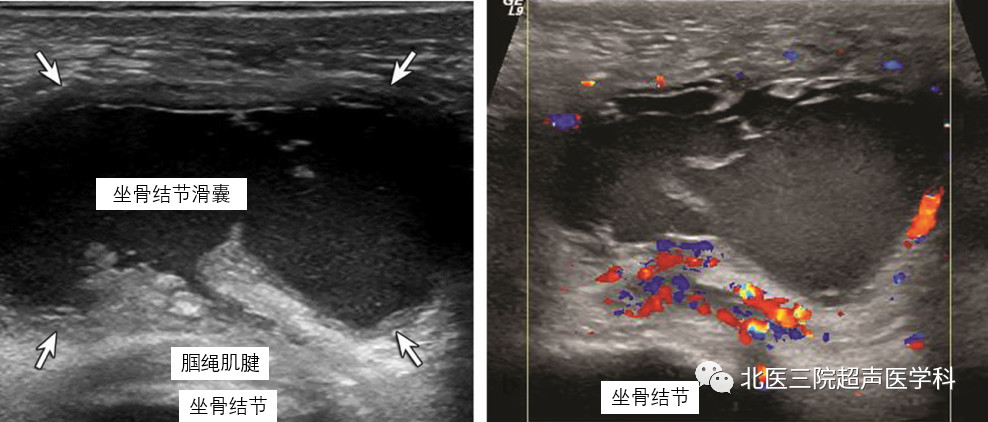

病例3--66岁女性,坐骨结节滑囊炎。灰阶(左图)及彩色多普勒(右图)超声显示位于腘绳肌腱浅方扩张的坐骨结滑囊。